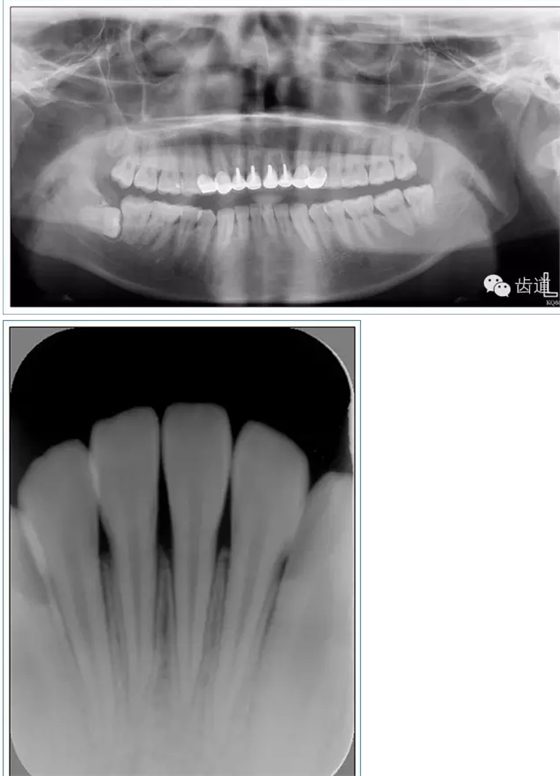

正壓力:即修復(fù)體的密貼程度(小于0.2mm)

表面粗糙程度

牙的外形及洞形的幾何形狀:主要是牙體制備出一定聚合角度產(chǎn)生的阻擋作用